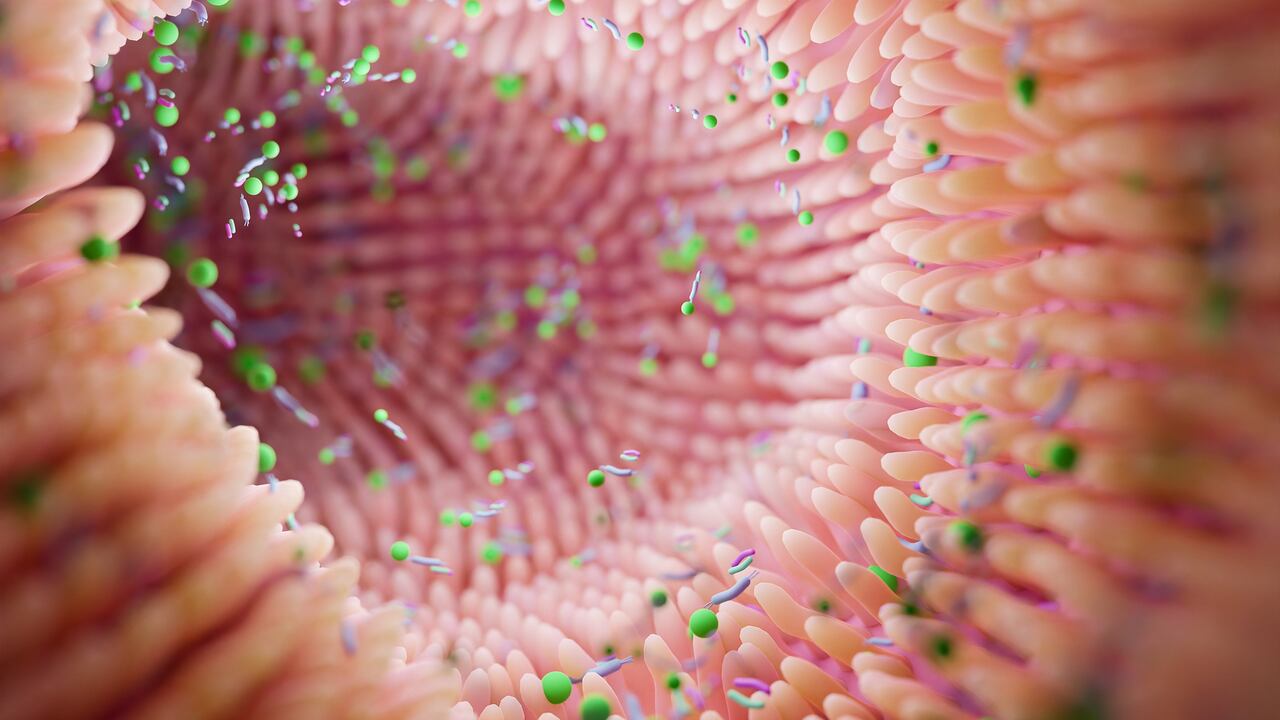

La flora o microbiota intestinal, como también se le conoce, es clave para el organismo, pues se encarga de defenderlo de bacterias, virus o enfermedades, además de asegurar el correcto funcionamiento del sistema digestivo y colaborar en la producción de vitaminas y la adecuada absorción de minerales.

Es un conjunto de microorganismos que vive en perfecta simbiosis en el intestino. La microbiota cumple con funciones clave. Una es la nutricional, que favorece la síntesis de compuestos como las vitaminas, entre ellas la K y las del grupo B; facilita la absorción de calcio y hierro en el colon, y favorece el movimiento intestinal.

De igual forma, estos microorganismos impiden la implantación de bacterias patógenas externas que puedan provocar infecciones y, por último, cumplen con una tarea inmunológica, en la que este conjunto de bacterias activa y fortalece el sistema inmunológico.